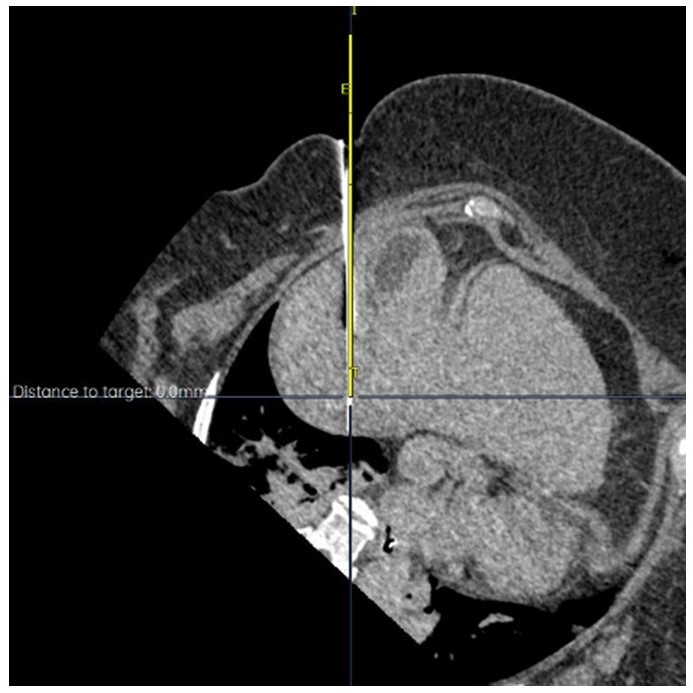

Dr. Berman’s academic and clinical career is distinguished by a strong commitment to innovation in minimally invasive cancer therapy. He has played pivotal roles in numerous clinical trials investigating emerging locoregional and immuno-oncology strategies, including investigator positions in the CapTemY90 trial and other advanced-phase studies for neuroendocrine tumors, HCC, and pancreatic cancer. He has authored over 30 peer-reviewed publications and book chapters, including work on Y-90 dosimetry, intraoperative embolization, and imaging response assessment, and has been recognized with honors such as “Top Doctor” in San Diego Magazine and the UCSD Resident Teaching Award.

A respected voice in the field, Dr. Berman has delivered over 60 invited lectures nationally and internationally, including at major conferences such as the Society of Interventional Oncology (SIO), Society of Interventional Radiology (SIR), and Western Angiographic Society. He has led sessions on personalized Y90 dosimetry, tumor ablation, and strategies for combining local therapies with systemic treatments. His educational leadership is evident through his involvement in SIR’s Residency Essentials Council, the SIO Education Committee, and as a site mentor for students and residents.